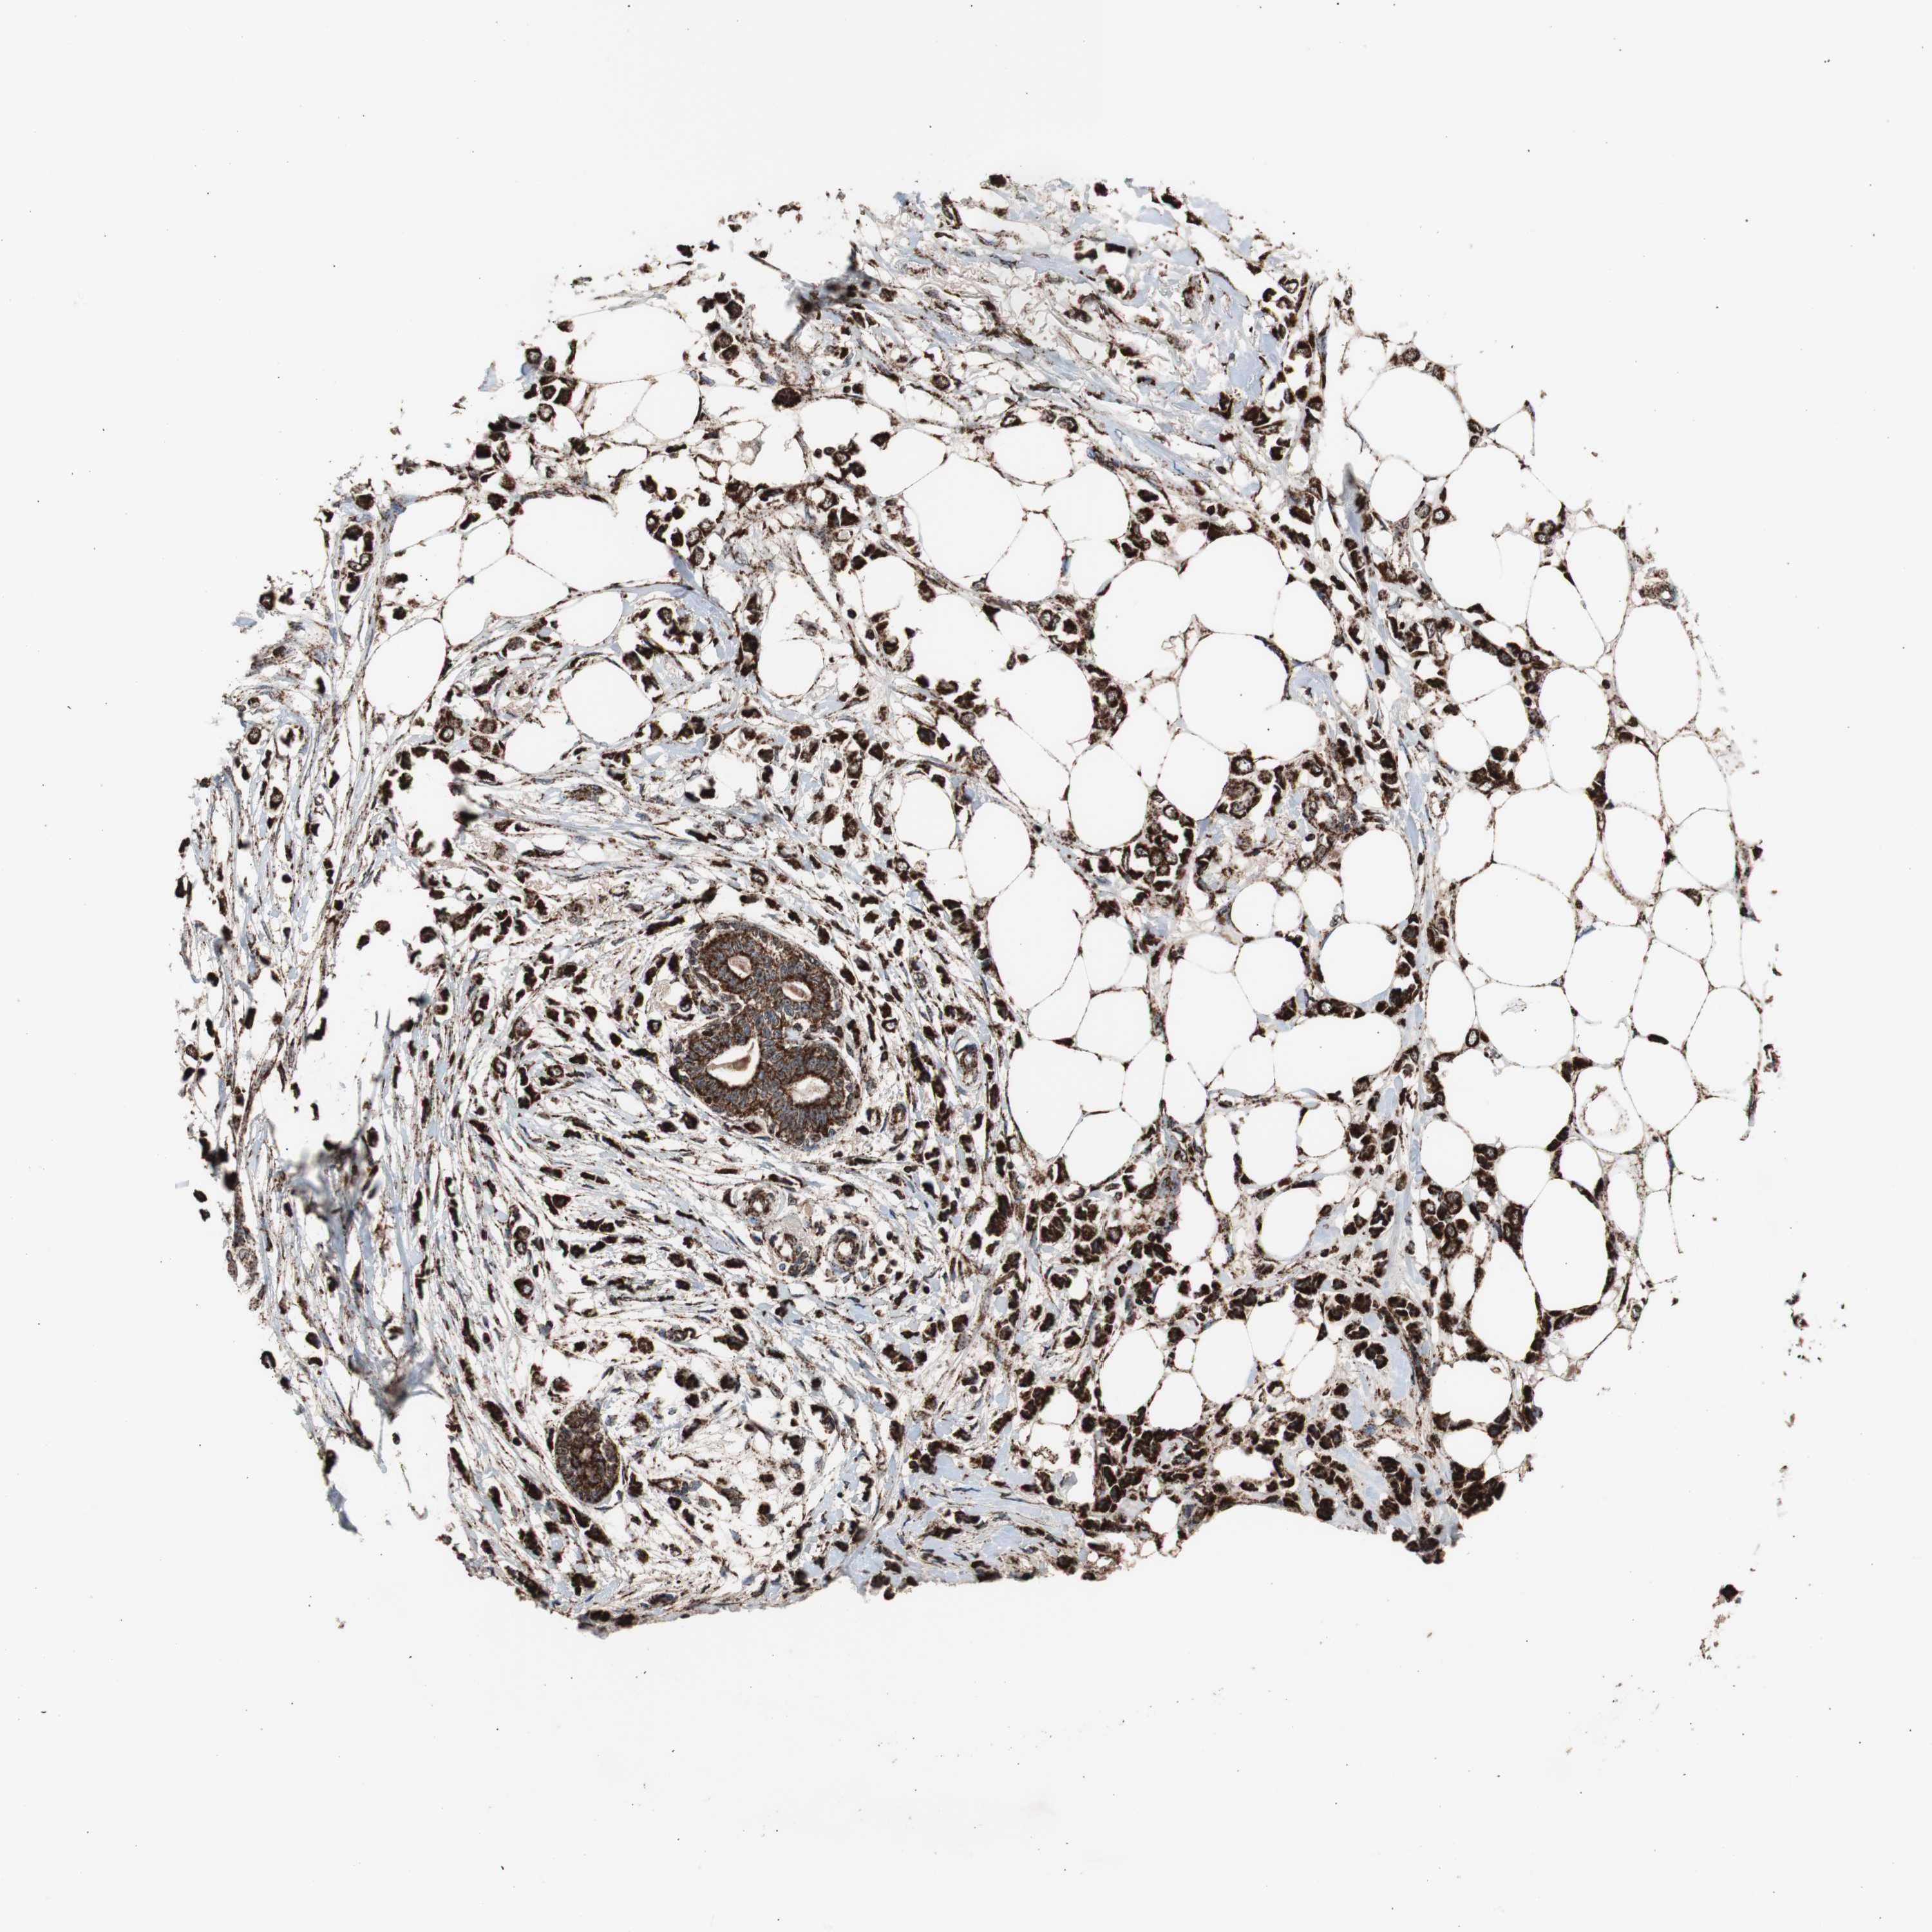

BRCA TCGA BRCA VALIDATION PROTEIN EXPRESSION

Breast cancer

Human cancer